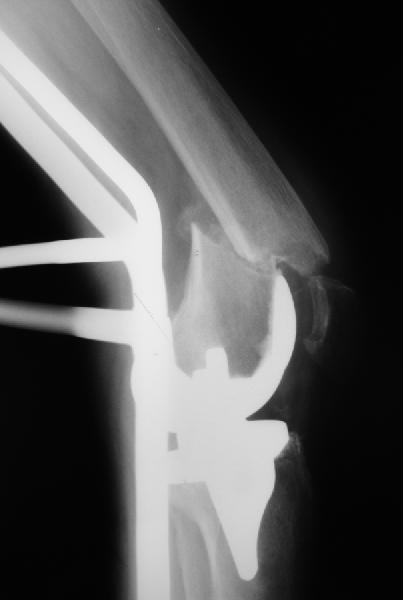

Поступила больная с перипротезным переломом

Перипротезный перелом у пациентки 67 лет . Эндопротезирование год назад . Сопутствующие нарушения ритма сердца и вес 120 кг при росте 185 .Думаю о мыщелковой пластинке с угловой стабильностью рыбинского исполнения остальное больной не потянуть . Заранее всем спасибо !

То, что планируется - наиболее распространенный подход. Еще менее инвазивный вариант - закрытый антеградный интрамедуллярный остесинтез. Мы используем гвозди, которые выпускаются предприятием ЦИТО, т.е. недорогие. Там в дистальное отверстие можно ввести 3 винта (2 снаружи и один навстречу), еще и угловая стабильность получается.